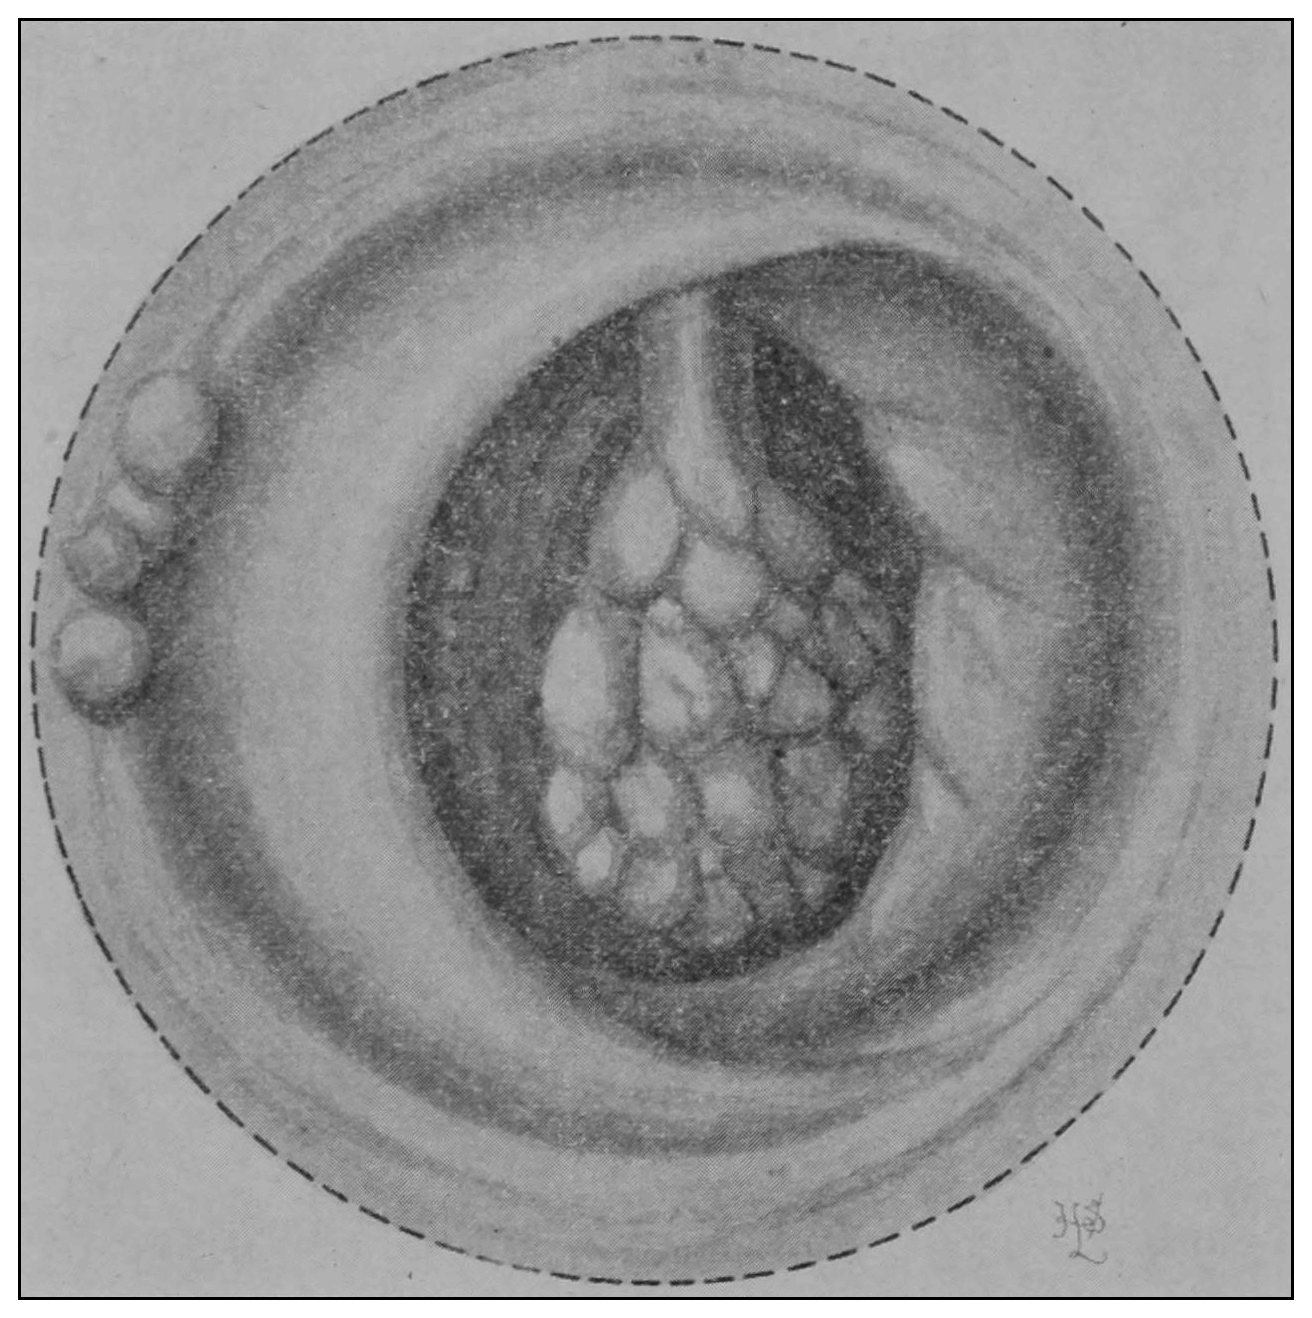

The rectum may present to the eye of the imaginative observer the appearance of a chain of urinary bladders, communicating one with another by means of irregularly elliptic openings set at varying axes, and bounded by the nonparallel borders of the rectal valves. In the normal rectum the air-pressure smooths the mucous membrane evenly over the entire surface of the gut, as may be observed in the photographic illustrations. The normal mucous membrane of the so-called ampulla appears at first wet and of a shining bluish gray. As it dries, under the influence of gravitation the blue venous tint fades out of the gray and the wall assumes a pink tint.[39] Presently it acquires the appearance of parchment, and sometimes it appears painted at rare intervals with ramifying little arteries which may be crowded and overlapped by the larger companion veins; the latter are less arborescent and more suddenly dive and disappear in the bowel-wall. In time, over all there comes a sheen and the vascular pictures may fade away. These phenomena appear exactly as described only in the healthy rectum. In the diseased organ the color varies much.

(c) The operator should observe the degree of rectal distention, the situation and number of the rectal[49] valves, their propinquity to one another when passive, and the relation of one valve to another at the time of the patient’s bearing down. Under pressure of the proctoscope if possible, or the hook if necessary, each valve should be effaced or displaced, and in regular order each of the rectal chambers should be carefully inspected. A proctoscopic mirror may be necessary for viewing the supravalvular surfaces (Fig. 18). The examination being finished: